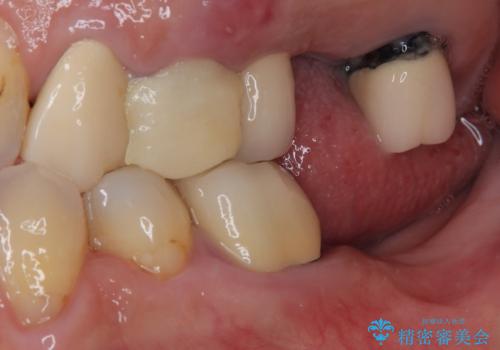

抜歯が必要な歯をインプラントに 短期間インプラント治療

- 抜歯が必要と言われ、インプラント治療を希望して来院された患者様です。

歯がボロボロで抜歯が必要な状態であり、後方にはインプラントが埋入されているため、同様にインプラントによる補綴治療を行うこととしました。

クラウンを装着できないため、プラスチックを歯に流し込んで仮歯のようにしている状態でした。

プラスチックを外すと同時に抜歯を行い、1ヶ月ほど待機して歯肉が落ち着いたことを確認してから速やかにインプラントを埋入することとしました。

従来は4ヶ月ほど待機してからの埋入が一般的でしたが、歯肉の炎症が落ち着いた時点で速やかに埋入できるようになり、4ヶ月の短期間で治療を終えることができました。